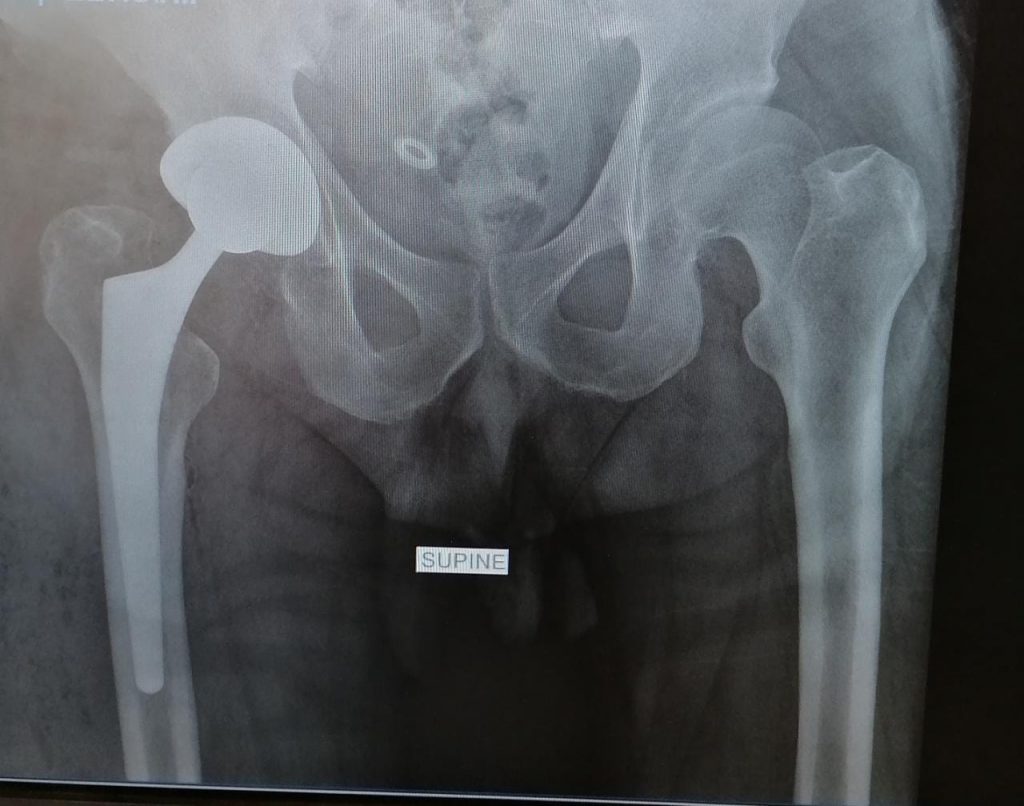

The replaced hip